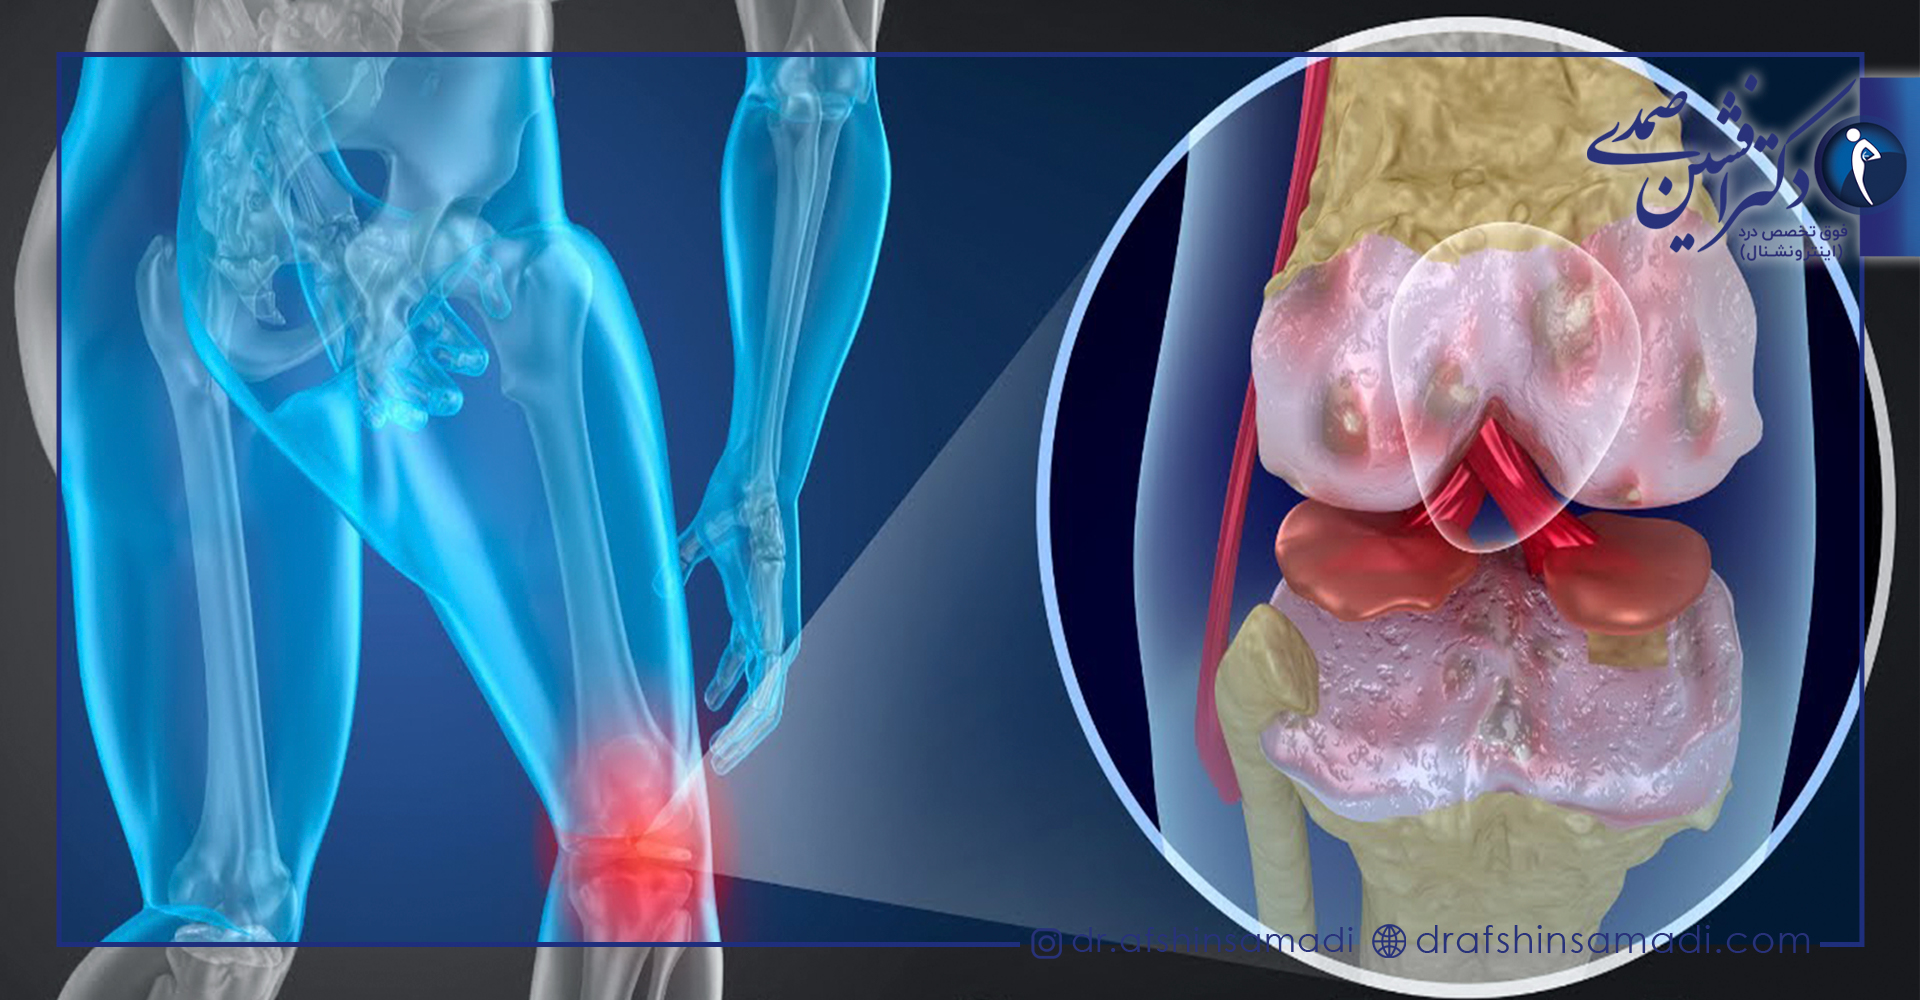

در بیماری استئوآرتریت غضروف میان مفاصل از بین رفته و استخوان های قسمت مفصل ها دچار آسیب دیدگی میشود.

این بیماری با ساییدگی، فرسودگی و از بین رفتن غضروف همراه است و در صورت ابتلا، فعالیت های روزمره شخص دچار مشکل می شود و باعث بروز درد می گردد.

زمانی که غضروف های موجود در انتهای استخوان ها دچار آسیب دیدگی شده و تحلیل روند، استئوآرتریت بروز می یابد و با از بین رفتن کاملا آن، دو استخوان بر روی همدیگر قرار گرفته و دچار ساییدگی میشوند.

این بیماری علاوه بر اینکه باعث تخریب غضروف می شود، بر روی کل مفصل های بدن اثر گذاشته و استخوان را دچار تغییر می کند.

ابتلا به آن بافت های نگهدارنده مفصل ها را از بین برده و التهاب پوشش مفصل را ایجاد می نماید.

وجود درد در مفصل های آسیب دیده در حین حرکت یا بعد از آن

متورم شدن مفصل ها به دلیل وجود التهاب در بافت های اطراف مفصل

داشتن حس ساییدگی در مفصل ها و صدای ترک خوردن

وجود خار های استخوانی که چون توده ای سخت هستند و در قسمت های اطراف مفصل آسیب دیده مشاهده می شوند.